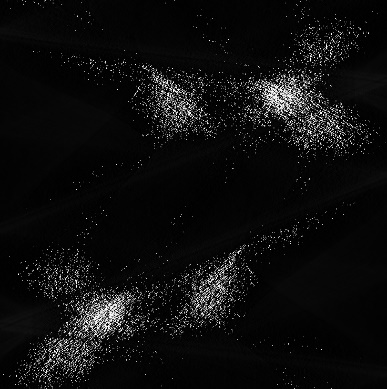

Low-Dose Computed Tomography (LDCT) technique, which reduces the radiation harm to human bodies, is now attracting increasing interest in the medical imaging field. As the image quality is degraded by low dose radiation, LDCT exams require specialized reconstruction methods or denoising algorithms. However, most of the recent effective methods overlook the inner-structure of the original projection data (sinogram) which limits their denoising ability. The inner-structure of the sinogram represents special characteristics of the data in the sinogram domain. By maintaining this structure while denoising, the noise can be obviously restrained. Therefore, we propose an LDCT denoising network namely Sinogram Inner-Structure Transformer (SIST) to reduce the noise by utilizing the inner-structure in the sinogram domain. Specifically, we study the CT imaging mechanism and statistical characteristics of sinogram to design the sinogram inner-structure loss including the global and local inner-structure for restoring high-quality CT images. Besides, we propose a sinogram transformer module to better extract sinogram features. The transformer architecture using a self-attention mechanism can exploit interrelations between projections of different view angles, which achieves an outstanding performance in sinogram denoising. Furthermore, in order to improve the performance in the image domain, we propose the image reconstruction module to complementarily denoise both in the sinogram and image domain.